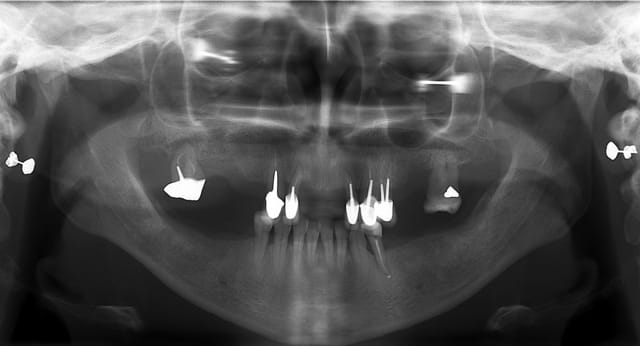

puor commencer complet in situ et guide radio...

Dsc 6073 pcexrz - Eugenol

Dsc 6077 ukfhsf - Eugenol

Smile beach jgh0a1 - Eugenol